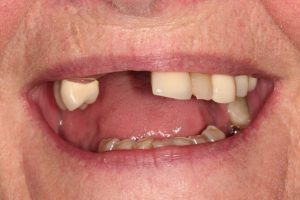

Upper Front Tooth Implant

This patient had broken their upper front tooth and the exisitng dental crown had fallen off. The underlying root was unfortunatley irreparable.

The dental root was subsequently removed and an implant placed at the same time. The implant had a temporary crown placedon the same day.

The ‘After’ photos shows the final crown that was made after 3 months. The implant crown was made to match the form and colour of the exisiting teeth to give an overall natural aesthetic finish.